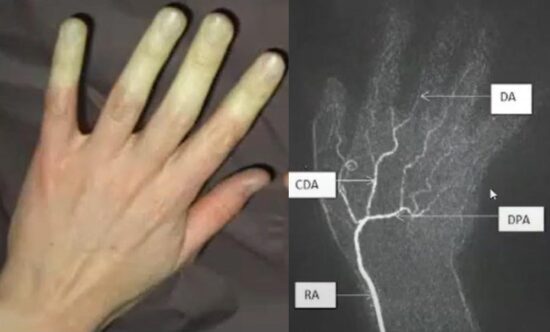

People who habitually operate vibrating machinery do get some fairly significant issues, in particular a very fairly well documented condition called hand-arm vibration syndrome (Figure F, top). It’s like a fairly severe form of Raynaud’s phenomenon, with some nerve and muscle damage. In this magnetic resonance angiography (Figure F, bottom), we see a complete occlusion of the ulnar artery which is what’s causing the fingers to go white, because the blood’s not getting down there, so we know for certain that as a result of vibration, we get nerve and muscle damage.